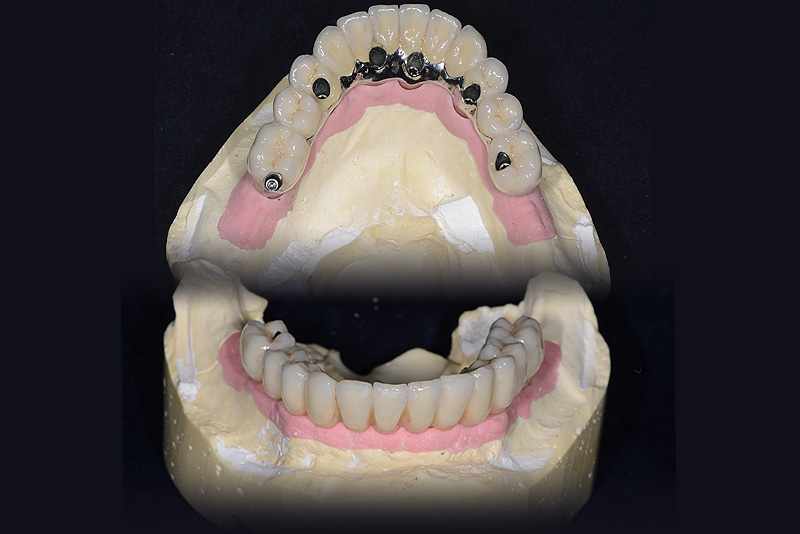

PREMESSA: in seguito all’estrazione dell’incisivo laterale superiore di destra, resasi necessaria per cause batteriche, si decide di affrontare il caso con il posizionamento di un impianto in sostituzione dell’elemento mancante dopo guarigione del sito infetto. Con tecniche rigenerative sia dei tessuti ossei mancanti a causa dell’infezione pregressa, sia dei tessuti gengivali che appaiono inizialmente troppo spostati in alto, si ripristina una corretta morfologia delle parabole (contorni) gengivali e delle papille interdentali (triangoli di gengiva tra due denti vicini).

Vengono utilizzati 2 tipi di provvisori: il primo, cementato ai denti vicini, viene utilizzato dal momento dell’estrazione del dente fino ad impianto osteointegrato (circa 6 mesi); il secondo, avvitato direttamente all’impianto, ha una funzione di prova estetica ma soprattutto di guida per la maturazione dei tessuti gengivali peri-implantari portandoli verso la maturazione completa prima di posizionare la corona finale in disilicato di litio.